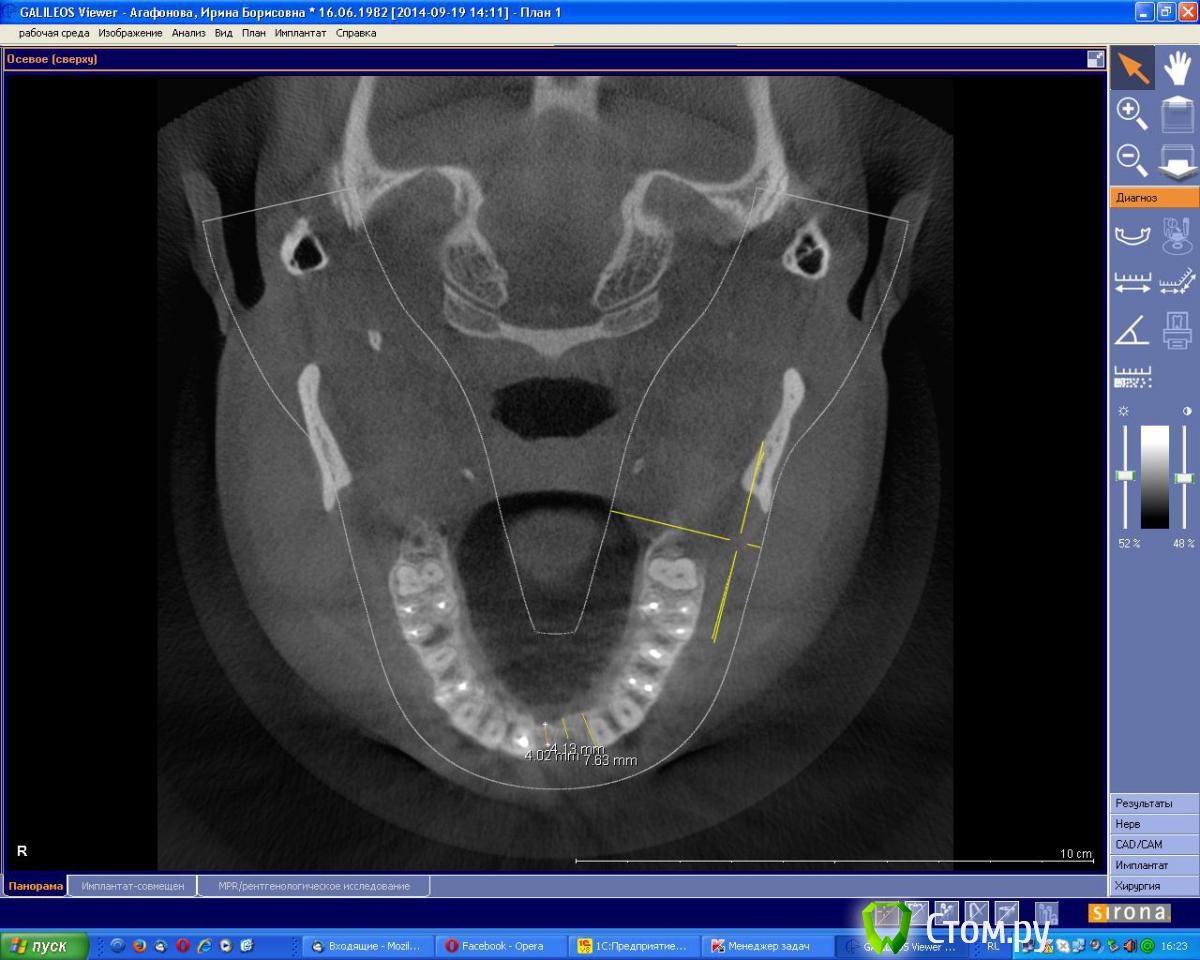

an_ver Опубликовано 19 сентября, 2014 Поделиться Опубликовано 19 сентября, 2014 (изменено) Молодая девушка,ранее был удален 21..с ее слов после удаления началось воспаление,выводили 2 месяца.После удаления-выведения прошло 6 месяцев. Сейчас фиксирован адгезивный мост. Вот такую картину имеем на сегодня. Что посоветуете,коллеги.Девушка хочет зуб Изменено 19 сентября, 2014 пользователем an_ver Ссылка на комментарий

an_ver Опубликовано 2 октября, 2014 Автор Поделиться Опубликовано 2 октября, 2014 Пики есть, уровень тоже. Согласен с Alexey Dok и faity, тут любая техника сработает от мембранной до ламината. Если эстетика немаловажна - VIP-CT или чего попроще.VIP на графт,сверху мембрану? Ссылка на комментарий